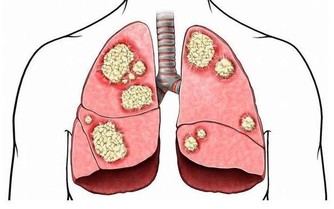

現代醫學已研討證實,過度的菸酒,可致使全身許多器官受損,致使180多種多見疑難病。若要從根本上解決疑問,仍是得管好嘴巴,餓餓肚子。